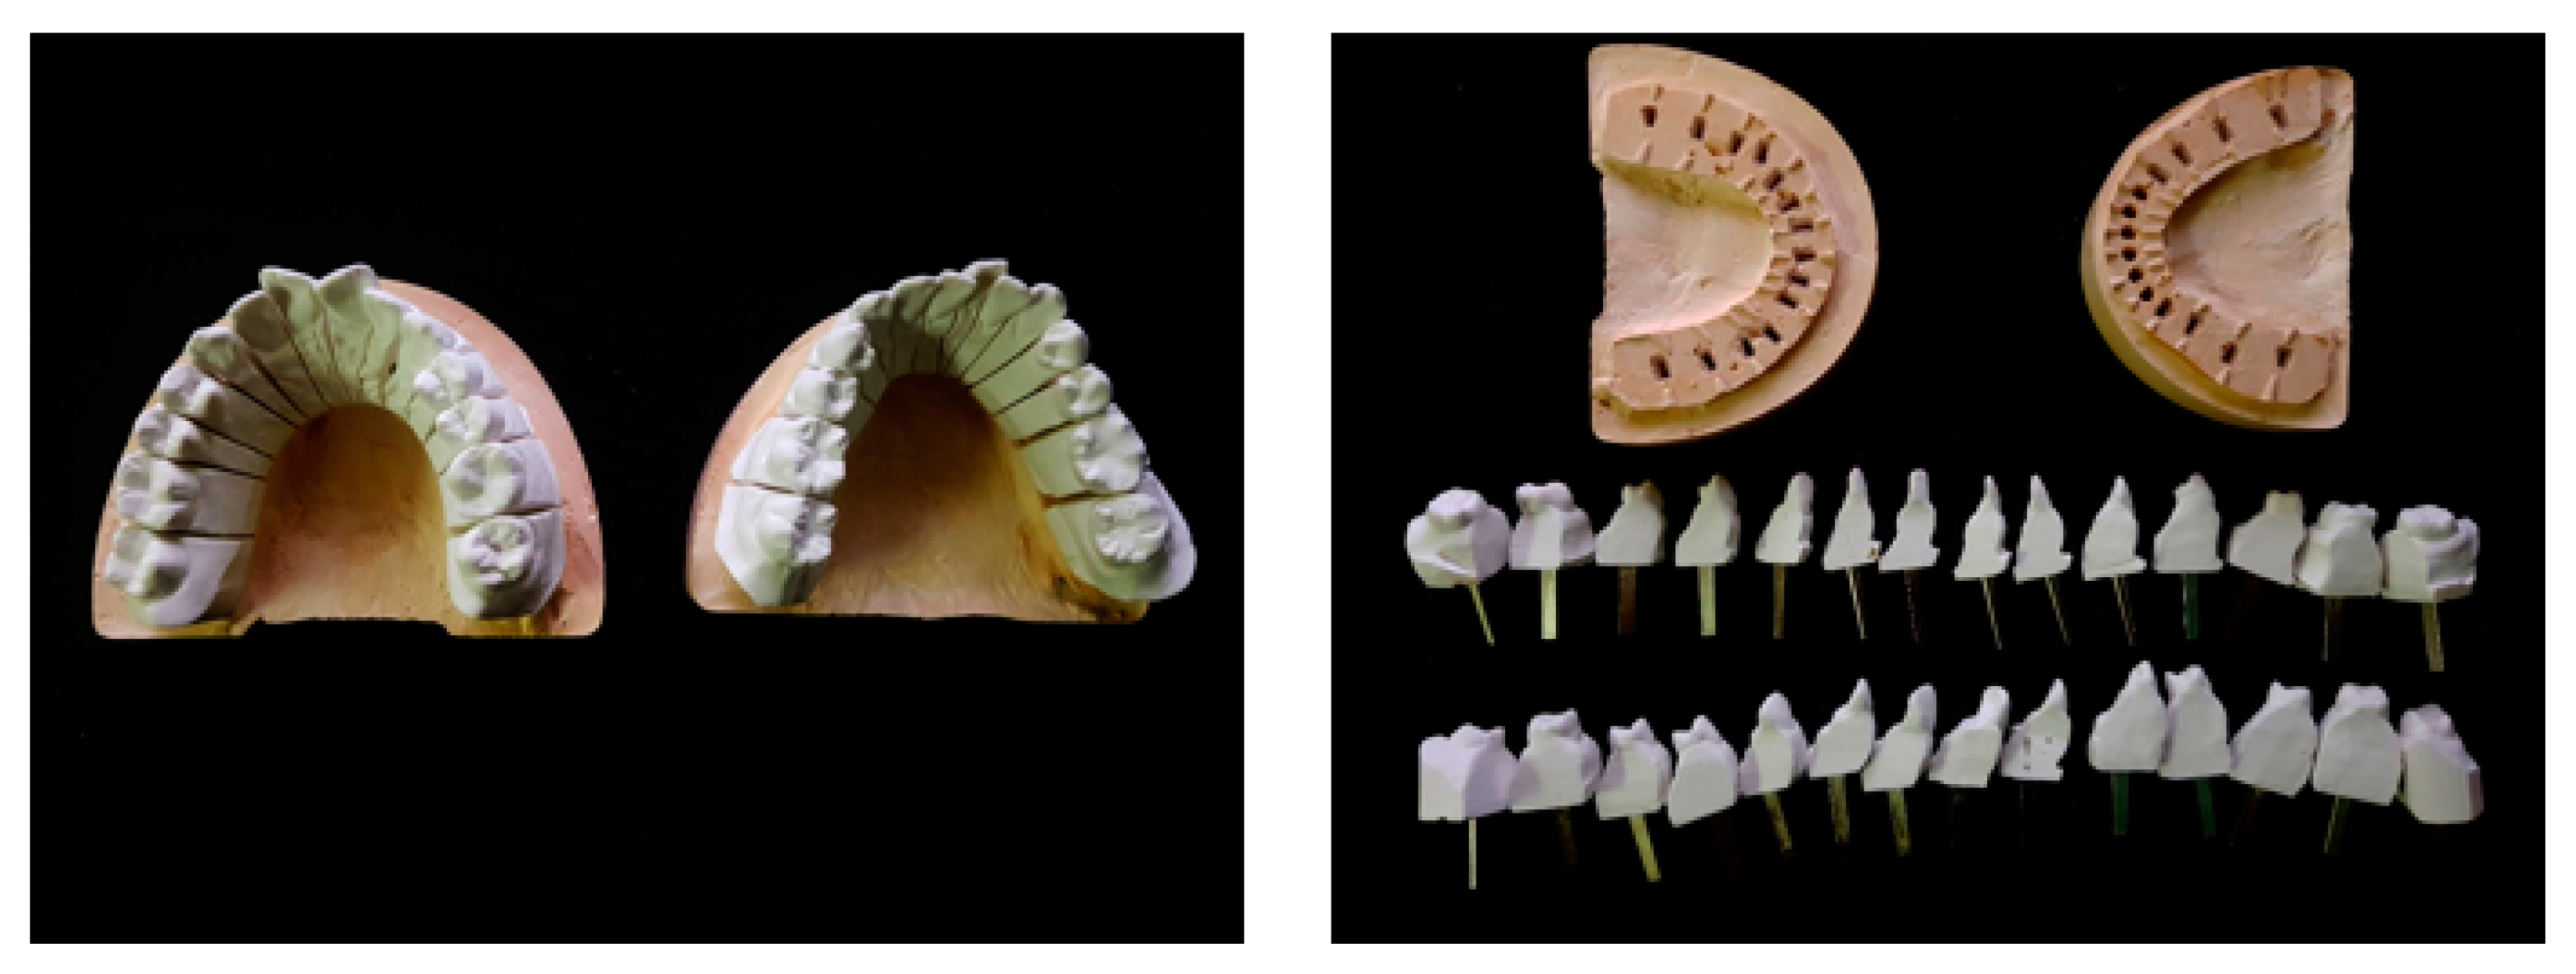

2.2. Reconstruction of Dental Scan Data

2.3.1. Data Preparation

3.2.1. Tooth Model